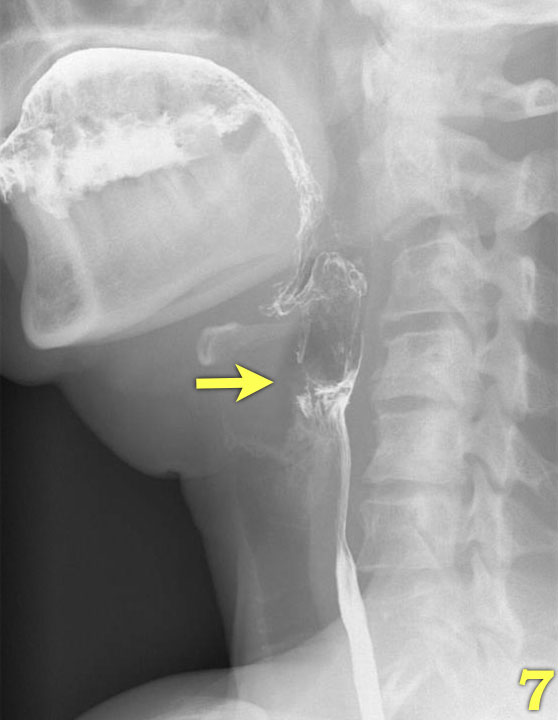

Các hình ảnh quan trọng nhất trong nghiên cứu nuốt là những hình ảnh chụp ở tư thế nghiêng (lateral view).

Nhấp qua các hình ảnh 1-7 ở bên trái.

- Nền lưỡi và vòm miệng mềm đóng khoang miệng ở phía sau (mũi tên) để ngăn thức ăn tràn vào hầu họng và thanh quản đang mở.

- Lưỡi bắt đầu vận chuyển thức ăn về phía hầu họng (mũi tên vàng).

Thanh quản vẫn còn mở và ở vị trí bình thường (mũi tên xanh lá). - Vòm miệng mềm nâng lên để ngăn thức ăn tràn vào vòm mũi họng (mũi tên xanh lá) và lưỡi đẩy thức ăn tiếp tục ra phía sau (mũi tên vàng).

- Xương móng nâng lên và thanh quản đóng lại (mũi tên xanh lá). Lưỡi đẩy thức ăn xuống dưới trong khi cơ khít thực quản trên co lại.

- Sự co thắt của cơ khít hầu giữa (mũi tên vàng), trong khi cơ nhẫn hầu đã giãn hoàn toàn (mũi tên xanh lá).

- Sự co thắt của cơ khít hầu dưới làm tống xuất hầu họng.

- Nắp thanh thiệt nâng lên để trở về vị trí nghỉ và thanh quản mở ra (mũi tên).